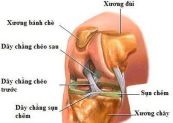

Chấn thương dây chằng chéo trước là tình trạng căng hoặc rách dây chằng. Tùy thuộc vào tình trạng nghiêm trọng và mức độ hoạt động, rách dây chằng có thể một phần hoặc hoàn toàn. Để hiểu rõ hơn về bệnh chấn thương này, mời các bạn tham khảo bài viết dưới đây!

Chấn thương dây chằng đầu gối có thể khiến bạn rất đau và hạn chế những hoạt động thường ngày. Bài viết dưới đây sẽ nói rõ hơn về triệu chứng, nguyên nhân và cách điều trị của chấn thương dây chằng đầu gối, mời các bạn tham khảo.